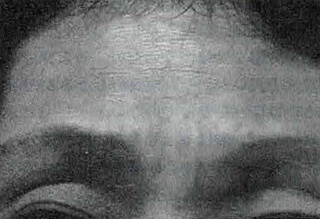

額と眉間の皺

ザイダームIIの注入により、2週間後には皺が目立たない程度に改善しています。

- 額と眉間の皺. 治療前/ZydermIIを注入

- 治療2週/眉間と額の皺は浅くなった